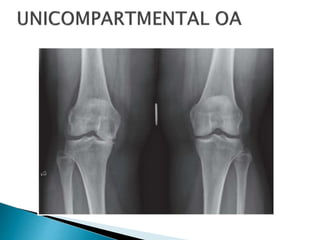

 Unicondylar OA

 Surgical management options for unicondylar

OA